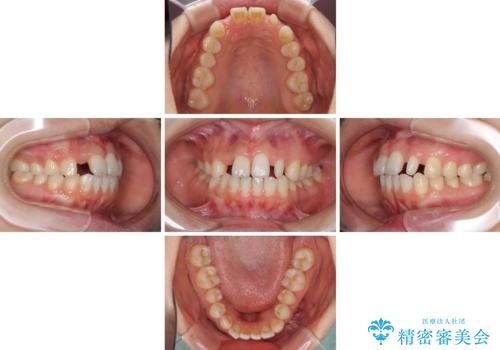

欠損歯と矮小歯 矯正治療と前歯のセラミック治療

- 前歯の隙間を気にして来院された患者様です。

診察の結果、前歯が1本欠損しており、さらに矮小歯(通常よりも小さい歯)が1本存在していました。

欠損による前歯のスペースが大きかったため、事前にワイヤー矯正で前歯の位置を大きく動かし、その後は上下をインビザラインで整えることとしました。

矯正治療後には欠損部はオールセラミックブリッジに、矮小歯はオールセラミッククラウンにて補綴することとしました。